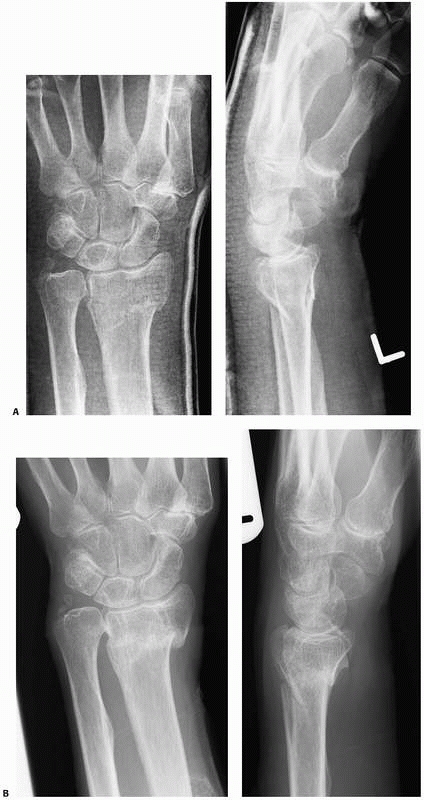

The Colles, or forearm cast, is the most widely used upper limb cast

and is used for most distal radial and ulnar fractures as well as for

some carpal injuries. The cast extends from below the elbow to just

proximal to the metacarpal necks of the digits with the thumb left free

(Fig. 6-16). The application of the Colles cast

is frequently preceded by the use of a dorsal plaster slab, which is

replaced by the cast once the swelling has reduced.

FIGURE 6-16 A Colles, or forearm, cast.